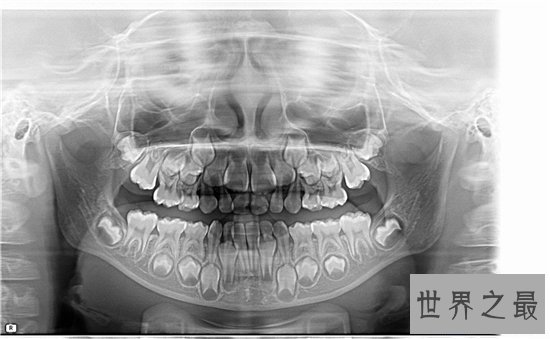

孩子是20颗牙齿,也就是说乳牙是20颗,而成年人是32颗。然而中国人有很多是没有最后四颗的,而这四颗是成年后长大的,也叫智齿。有的人不能长出,所以成年人的牙齿可能从28到32颗,但假设你拍摄X光片,你就可能看到它们。失常成年人只需没有被移除就会有32颗牙齿。

4、滞留的乳牙

有些小孩子在换牙期的时分恒牙已经萌出了,能够乳牙却不断保留在口腔内,这种情况就叫做乳牙滞留,乳牙滞留会将本来恒牙要萌出的地位被占领,这样容易使得恒牙错位萌出,惹起牙齿拥堵、错位等成绩。

5、多生牙

有些宝宝会出现牙齿中间出现多余的牙齿萌出,这样的多余牙会形成牙齿拥堵,因此,需求尽早停止拔除。